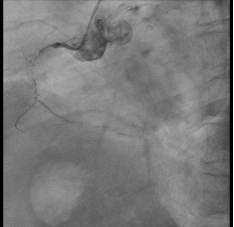

69岁的葛女士,1年前无明显诱因出现胸闷胸痛症状,呈压榨性疼痛,无放射痛,伴活动后气促,当时就诊于某医院,行左、右冠状动脉造影提示:LAD近中段90%狭窄,D1近段迂曲并有90%狭窄伴钙化。LCX中段完全闭塞;RCA全程钙化影,近段70-90%狭窄,中段完全闭塞,术中于前降支置入1枚支架。1周前葛女士再次出现活动后胸痛气短症状,伴背部放射痛,有胸闷、乏力,遂至我院就诊。

入院后完善冠脉造影提示多支血管狭窄较前进一步增加,进行MDT讨论后,决定行三根冠状动脉搭桥+冠状动脉内膜剥脱术。手术过程顺利,术后ICU过渡3日后转回普通病房,术后2周顺利出院。

患者冠脉造影图像